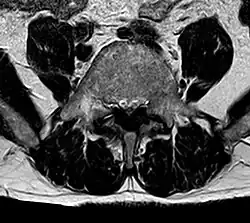

Die Ligamenta flava sind jeweils zwischen den Wirbelbögen ausgespannt und wurden deshalb früher auch als Ligamenta interarcualia bezeichnet. Sie grenzen damit das jeweilige Zwischenwirbelloch (Foramen intervertebrale) zur Mitte (medial) und nach hinten (dorsal) ab. Ihre gelbliche Farbe wird durch scherengitterartig angeordnete, elastische Fasern hervorgerufen, die zum größten Teil diese Bänder bilden. Auch im Ruhezustand sind diese Bänder gespannt. Bei der Beugung der Wirbelsäule werden sie dann stärker gedehnt und helfen somit beim Wiederaufrichten.

Eine Hypertrophie der Ligamenta flava kann (oft in Kombination mit anderen Faktoren) zu einer spinalen Stenose führen.